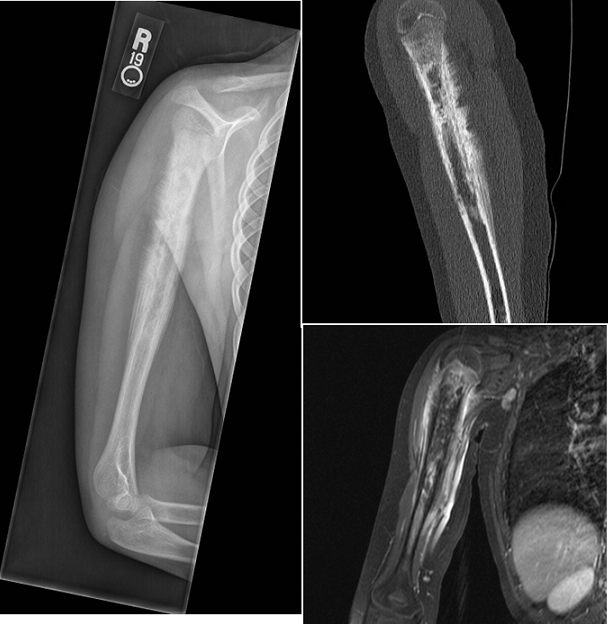

A 79-year old female presents with complaints of right hip pain for 2 months. She denies prior injury or precipitating event. The pain is made worse by lying on the affected side and occasionally hurts with hip motion. The pain is improved with NSAIDS and placing ice on the lateral aspect of her hip. Her primary care physician ordered x-rays which showed a bone lesion in the proximal femur. Her PCP was concerned she had bone cancer and ordered an MRI of the thigh to further evaluate. AP x-ray and a coronal MRI image are shown above. The patient denies a history of weight loss, fatigue, and history of cancer. On exam the patient has no pain with passive range of motion of the hip in all planes. She has pain with palpation over the greater trochanteric bursae. Motor and sensation are intact throughout the lower extremities. What is the most likely cause of this patient’s pain?